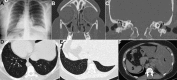

Kartagener's syndrome

Keywords: Kartagener´s syndrome; dextrocardia; sinusitis.